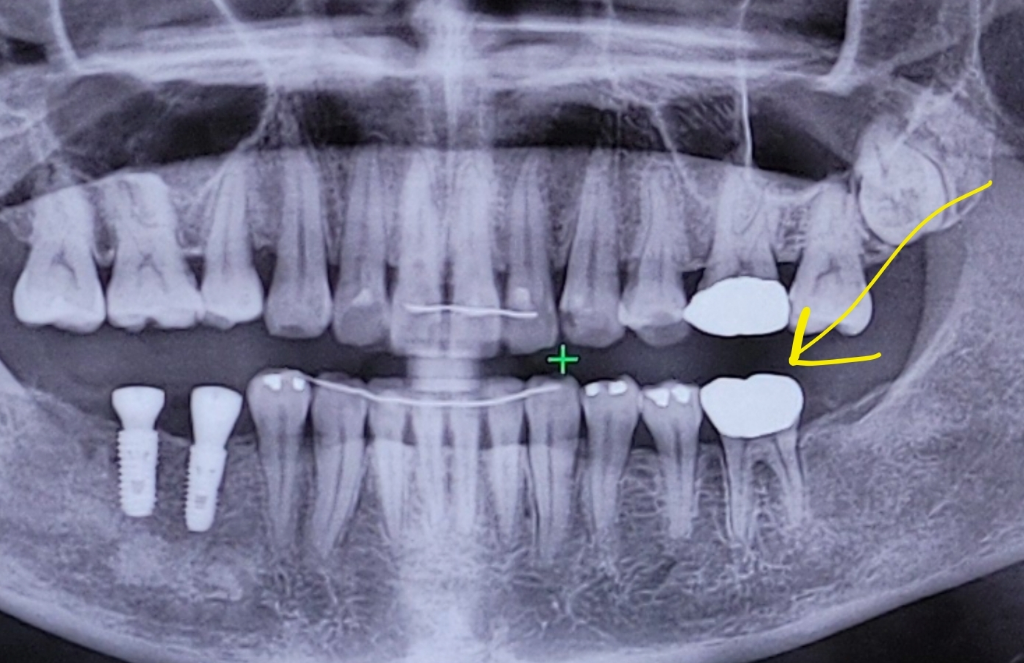

사진의 노란 화살표인 아래쪽 어금니입니다.

-사진은 골드 크라운 씌우고 직후 찍은 사진입니다.

-이후 1달 뒤, 염증이 생겨 잇몸에 콩알같이 틔어 나왔습니다.

사진상 1달 전 사진인데, 염증 생길 징후가 있었나요?